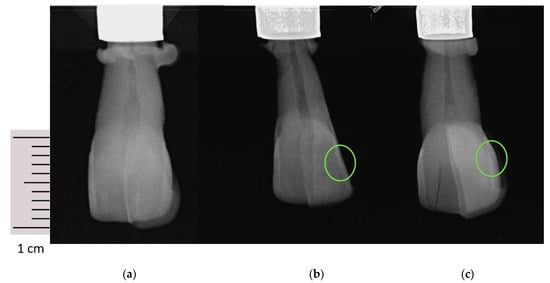

2.3. Radiological and Fluorescence Examination

| 0 | No visible radiolucency |

| 1 | Radiolucency in the outer half (<half of the enamel) |

| 2 | Radiolucency in the inner half (<half of the enamel up to the enamel-dentin border) |

| 3 | Radiolucency in the dentin (broken enamel-dentin border but without obvious spread in the dentin) |

| 4 | Radiolucency with obvious spread in the outer half of the dentin (<halfway through the pulp) |

| 5 | Radiolucency with obvious spread in the inner half of the dentin (>halfway through the pulp) |